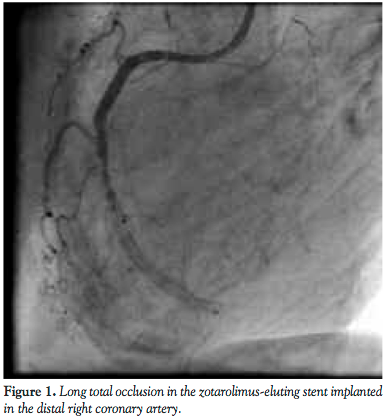

The coronary angiogram showed the left coronary system free of significant disease. However in the RCA a long total occlusion was seen in the Endeavor stents (Medtronic) implanted in the distal portion. Contrarily, in the proximally implanted Nobori stent, no restenosis was revealed. Furthermore, an intermediate de novo stenosis was also demonstrated in the mid RCA segment (Figure 1).